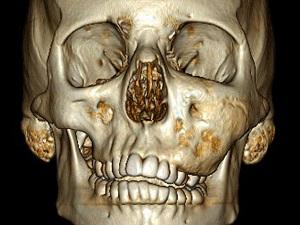

Череп и челюсти

Лечение фиброзной дисплазии костей черепа может включать как частичное, так и полное удаление пораженной области кости.

Показания для проведения хирургического вмешательства:

- быстрое развитие замещения соединительной тканью костей черепа;

- выраженный болевой синдром;

- заметные косметические изменения в области челюсти и головы;

- нарушения функциональности костей.

Основная цель операции при фиброзной дисплазии челюсти заключается в устранении выпячивания костей, предотвращении дальнейшего разрастания соединительной ткани и уменьшении деформации суставов.

В 8-10% случаев наблюдаются рецидивы после трансплантации. В большинстве случаев пациенты отмечают значительное улучшение состояния и восстановление функций челюстных и черепных костей.

Какое исследование проводится для подтверждения диагноза фиброзная дисплазия скуловой кости?

Основным инструментом для диагностики фиброзной дисплазии является компьютерная томография.